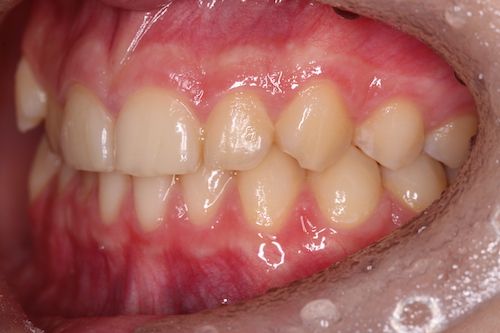

До